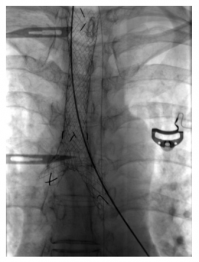

She was doing well for six months; however, she presented to emergency with history of cough, fever and wheeze for 15 days. On evaluation, she had type 2 respiratory failure and needed biphasic positive airway pressure support. Also, she was given high-dose steroids under antibiotics cover. HRCT of the chest showed worsening as expected. There was no improvement with the existing treatment even after three weeks. Patient continued having carbon dioxide retention with high respiratory rate and deterioration of sensorium despite noninvasive ventilation support. She also developed hospital-acquired infection. Discussion with the respiratory team and relatives ensued and decision for tracheal stenting was established (Figures 3 and 4).

Earlier stenting was avoided in view of long segment involvement. Post-procedure, she was put on ventilator and tracheostomized later in view of long-term ventilatory involvement. She was discharged after three weeks of hospital stay and later she suffered from post-procedure complications like tracheostomy site ulcer and its bleeding, subcutaneous emphysema and difficulty regaining activities of daily living. She was readmitted after a month with worsening of breathlessness and fever and was bound to have bilateral pneumonia. This time, she succumbed in view of sepsis and related acute kidney injury.